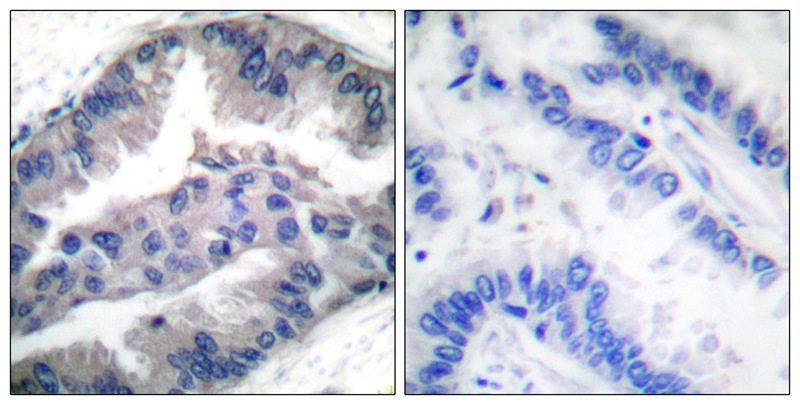

分类: 科研抗体货号: P40746别名: double minute 4 protein; Mdm2-like p53-binding protein; MDMX; p53-binding protein Mdm4应用: WB,IHC反应种属: Human,Mouse,Rat